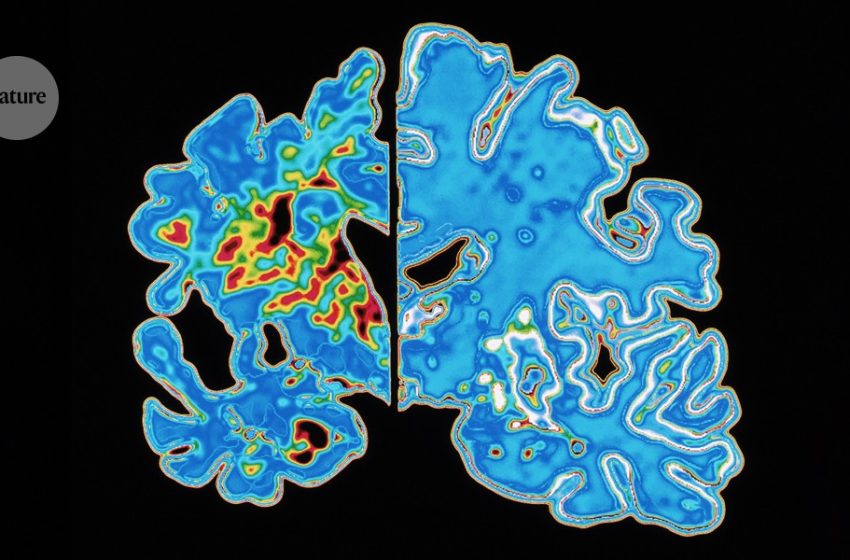

Abnormal tau proteins can form tangled fibres that accumulate in the brains of people with Alzheimer’s (slice at left). (Brain without Alzheimer’s shown at right.)Credit: Alfred Pasieka/Science Photo Library

Abnormal tau proteins can form tangled fibres that disrupt communication among the brain’s nerve cells. Brain-imaging tests that detect tangled tau are sometimes used when diagnosing Alzheimer’s, and preliminary studies suggest that such tests might also be able to predict when a person’s Alzheimer’s symptoms will appear2,3.